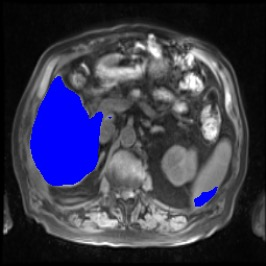

Integrating high-level semantically correlated contents and low-level anatomical features is of central importance in medical image segmentation. Towards this end, recent deep learning-based medical segmentation methods have shown great promise in better modeling such information. However, convolution operators for medical segmentation typically operate on regular grids, which inherently blur the high-frequency regions, i.e., boundary regions. In this work, we propose MORSE, a generic implicit neural rendering framework designed at an anatomical level to assist learning in medical image segmentation. Our method is motivated by the fact that implicit neural representation has been shown to be more effective in fitting complex signals and solving computer graphics problems than discrete grid-based representation. The core of our approach is to formulate medical image segmentation as a rendering problem in an end-to-end manner. Specifically, we continuously align the coarse segmentation prediction with the ambiguous coordinate-based point representations and aggregate these features to adaptively refine the boundary region. To parallelly optimize multi-scale pixel-level features, we leverage the idea from Mixture-of-Expert (MoE) to design and train our MORSE with a stochastic gating mechanism. Our experiments demonstrate that MORSE can work well with different medical segmentation backbones, consistently achieving competitive performance improvements in both 2D and 3D supervised medical segmentation methods. We also theoretically analyze the superiority of MORSE.